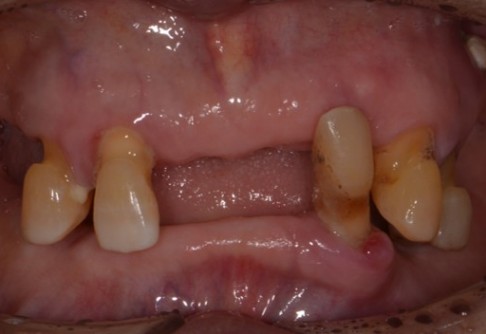

Before

After

위 치료 사례는 굿프렌즈치과에서 직접 치료를 받은 환자 분의 사례로 직접 동의를 얻어 게재되었습니다.

치료사례 더보기 +